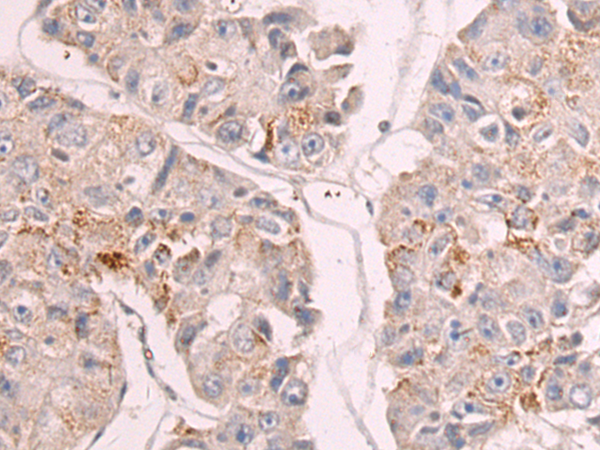

Immunohistochemistry analysis of paraffin-embedded Human liver cancer using GDF9 antibody. High-pressure and temperature Sodium Citrate pH 6.0 was used for antigen retrieval.